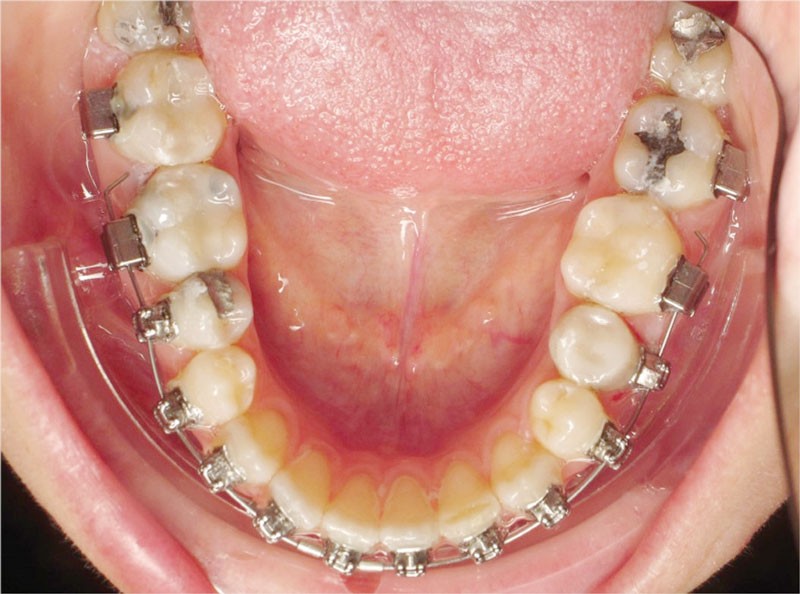

La patiente demande des attaches céramiques et nous trouvons un compromis en lui proposant un appareillage Insignia Damon Clear au maxillaire et Damon métallique à la mandibule.

L’avantage des brackets métalliques en technique Insignia est l’individualisation complète des informations des 1er, 2e et 3e ordres (torque individuel suivant set up).

Des surélévations postérieures par cales sont posées et nous avons prévu un port d’élastiques précoce 23 heures sur 24.

La séquence d’arcs et d’élastiques est la suivante :

– 0.014 cuniti standard Damon + élastiques Parrot en trapèze pendant 2 mois

– 14×25 cuniti custom suivant set up + tim moose en box pendant 2 mois

– 18×25 cuniti custom suivant set up + Moose box /arc-en-ciel pendant 2 mois

– 19×25 Tma > 16×25 tma< custom suivant set up